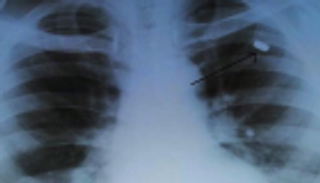

وغطت كرة الشعر مساحة 8 X 20 سنتيمترا. وتم إزالتها باستخدام منظار البطن، أي جراحة بالمنظار ثلاثي الأبعاد عبر جدار المعدة.